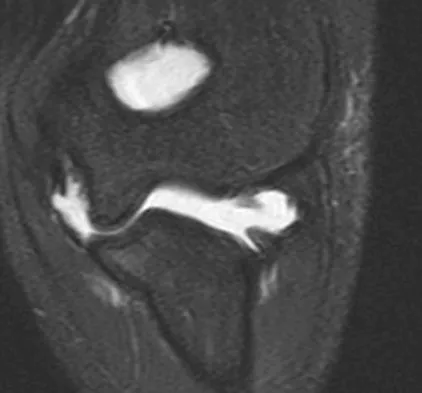

An MRI arthrogram of the elbow is shown in Figure 6. Based on these findings, what is the most likely diagnosis?

Explanation

MRI arthrography is the imaging study of choice for evaluation of medial collateral ligament injuries. Carrino JA, Morrison WB, Zou KH, et al: Noncontrast MR imaging and MR arthrography of the ulnar collateral ligament of the elbow: Prospective evaluation of two-dimensional pulse sequences for detection of complete tears. Skeletal Radiol 2001;30:625-632.